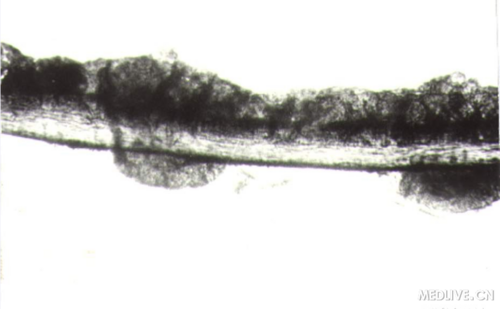

腋毛菌感染(光镜-毛发表面菌丝)